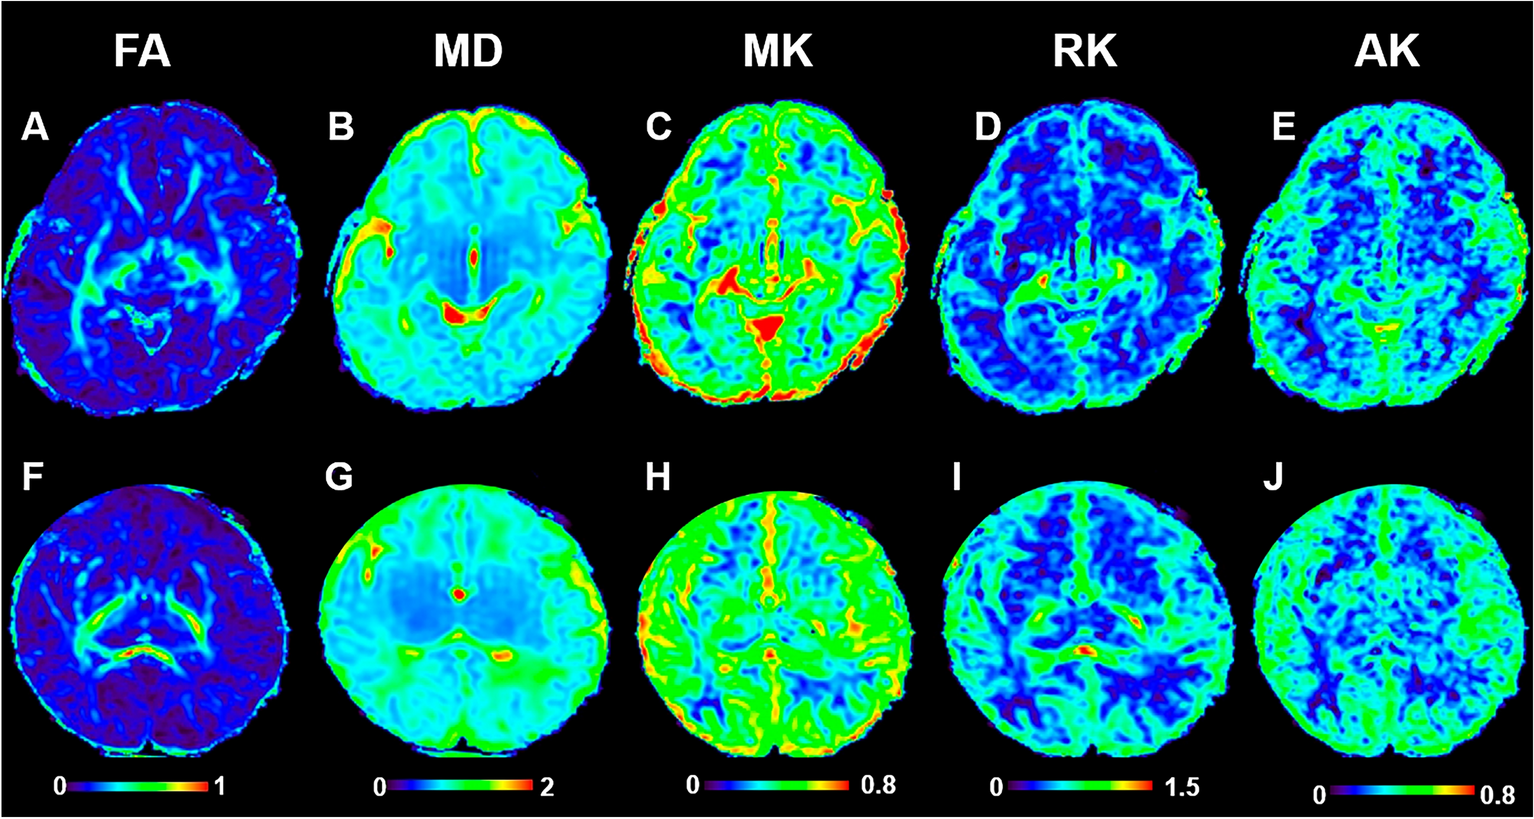

Figure 3

DKI images of preterm infant brain with low-grade IVH and without IVH. FA, MD, MK, RK and AK images of preterm infant brain without low-grade IVH (A–E) and with low-grade IVH (F–G). The two cases were all male, 40 weeks. fractional anisotropy, FA; mean diffusivity, MD; mean kurtosis, MK; radial kurtosis, RK; axial kurtosis, AK.